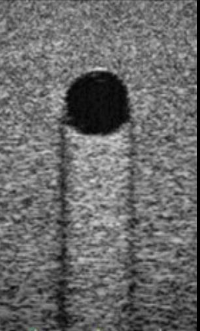

This image displays a

simple cyst